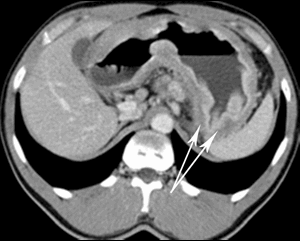

(Слева) На рентгенограмме, выполненной при рентгеноскопии верхних отделов ЖКТ у трехлетней девочки, у которой наблюдается рвота, определяется фиксированный дефект наполнения в желудке с «вихревым» рисунком за счет наличия газа и включений солидного характера, обусловленный наличием трихобезоара.

(Справа) На рентгенограмме, полученной при исследовании пассажа бариевой взвеси по тонкой кишке, определяются признаки ранее выполненной резекции желудка по Бильрот 2, а также полное отсутствие прохождения бариевой взвеси в средние отделы тощей кишки (антеградно). Во время операции был удален фитобезоар, по своей форме и размерам сопоставимый с культей желудка.